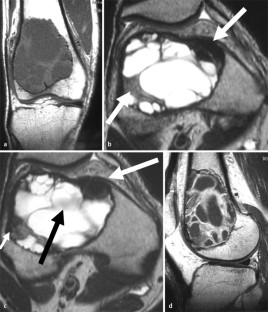

MRI morphology of bone tumors and tumor-like lesions

Für das Staging und die Charakterisierung von Knochentumoren und tumorähnlichen Läsionen ist in der Magnetresonanztomographie (MRT) der Einsatz von Spinechosequenzen erforderlich. Die MRT hat nur einen geringen Stellenwert in der Bestimmung der Dignität. Obwohl viele Knochentumoren und tumorähnliche Läsionen eine vergleichbare Morphologie in dieser bildgebenden Modalität aufweisen, können einige Tumorentitäten mittels MRT recht zuverlässig diagnostiziert werden. Hierzu zählen Knorpeltumoren, die solitäre und aneurysmatische Knochenzyste, der Riesenzelltumor, fetthaltige Läsionen und bis zu einem gewissen Grad auch das Osteoidosteom und das Osteoblastom. Es werden praktische Tipps gegeben, wann bei Tumorverdacht die MRT eingesetzt werden sollte, wie bei einem zufällig bei einer MRT gefundenen Tumor die Untersuchung modifiziert werden sollte und welcher Tumor vorliegen könnte.

Spin-echo sequences are mandatory at MRI for staging and characterization of bone tumors and tumor-like lesions. MRI is of minor value in the estimation of the malignant potential of an osseous lesion. Although many bone tumors and tumor-like lesions present similar morphology at MRI, some entities can be diagnosed with good reliability. These include chondrogenic tumors, solitary and aneurysmal bone cysts, giant cell tumors, lesions containing fatty tissue and, to a certain extent, osteoid-osteomas and osteoblastomas. Practical advice is given regarding when to perform a MRI study in cases of tumor suspicion. Further advices are given for cases a tumor is found incidentally at a MRI study, how to modify the study and which kind of tumor may be present.